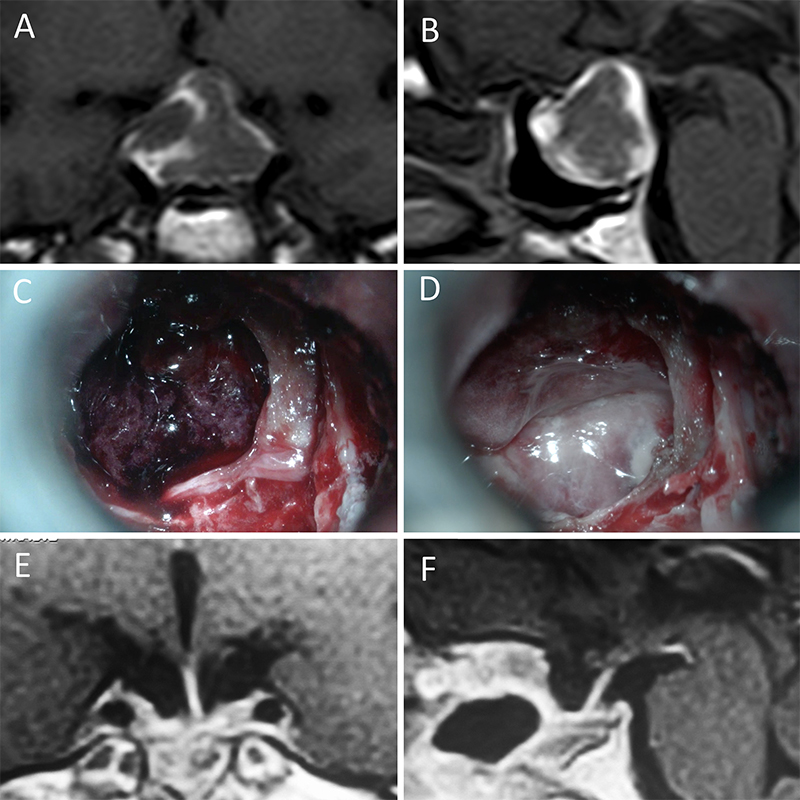

Presentamos 15 casos ilustrativos que consideramos representativos de nuestra serie: 4 enfermos con macroadenomas no funcionantes (figs. 1 a 4); 2 pacientes con macroadenomas con apoplejía (figs. 5 y 6); 4 enfermos con acromegalia (figs. 7 a 10); 3 pacientes con enfermedad de Cushing (figs. 11 a 13) y 2 enfermos con prolactinomas (figs. 14 y 15). El detalle de la presentación clínica de cada paciente y su correspondiente evolución postoperatoria se detalla en el epígrafe de cada ilustración.

Figura 5: Apoplejía hipofisaria hemorrágica en un hombre de 32 años. El paciente presentó cefalea y parálisis completa del III par. Tuvo restitutio ad integrum en el seguimiento. A-B: RM preoperatoria; C-D: intraoperatorio; E-F: RM postoperatoria.

Figura 6: Apoplejía hipofisaria hemorrágica en un hombre de 55 años. El paciente presentó cefalea, déficit visual y parálisis completa del III par. Evolucionó favorablemente tras la cirugía, revirtiendo el cuadro. A-B: RM preoperatoria; C-D: intraoperatorio; E-F: RM postoperatoria.